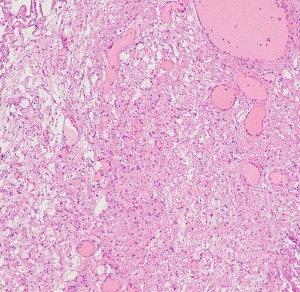

紡錐型の核を有する腫瘍細胞で構成されます。左側の写真のように,古典的病理所見として,束状 fascicular に配列する密な組織である Antoni A Typeと網状 reticular で疎な組織である Antoni B Typeが混在するパターンを示します。神経鞘腫では多少の核の異型性がみられても悪性像とはいえません。嚢胞を形成したり,時には毛細血管拡張 simple hemangioma を思わせるような著明な血管の増生があり腫瘍内出血をきたすことがあります。

30代男性の迷走神経鞘腫です。右のように活発に増殖してstreaming patternをとる部分と,左のようにのう胞形成しながら退縮変性 degenerative change している部分が混在しています。若年者の神経鞘腫でも退縮変性はみられます。